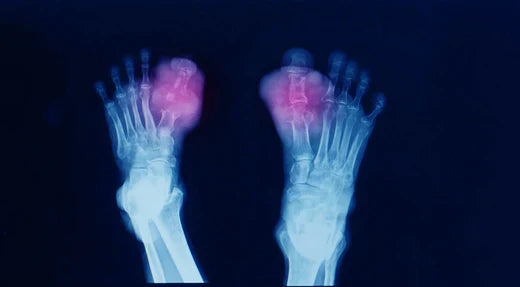

Tophaceous gout is an advanced, chronic stage of gout that develops when elevated uric acid levels remain uncontrolled for many years. Over time, excess uric acid forms monosodium urate crystals that accumulate in and around the joints. These deposits create visible nodules called tophi.

Without proper treatment, tophaceous gout can damage cartilage, erode bone, and significantly impair joint mobility. The condition most commonly affects the feet—especially the big toe—as well as the ankles, hands, and elbows.

Diagnosis involves clinical evaluation and imaging studies to confirm urate crystal deposits and assess joint damage.

X-rays, ultrasound, or dual-energy CT scans to identify tophi and structural changes